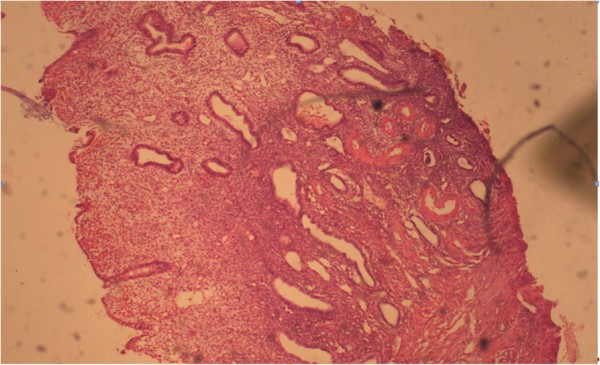

According to our findings, uterine polyp is a local lesion of exophytic growth, derived from the basal layer of the endometrium. In the early stages of development, polyps look like small proliferates located in the basal section of the endometrium on the verge of the myometrium. Microscopically, these foci are different from the surrounding normal endometrium disordered clusters of tubular and glandular structures with low row indifferent epithelium type, surrounded by a dense cellular stroma. The basal growth area of glandular proliferation penetrates the upper layers of the endometrium, pushing them through expansive growth and bulges above the surface as exophytic lesion. The surface of the polyp is often covered with a layer of functional endometrium that participates in the cyclic changes as the neighbouring endometrium and is rejected in phase desquamation. A hysteroscopic imaged of intrauterine lesions: endometrial polyp and submucosal fibromyoma are shown in Figure 6. Histology of one type of polyp, namely glandular cystic polyp, is shown in Figures 7 and 8.

Figure 7

Glandular cystic endometrial polyp. Coloring by hematoxylin-eosin (×40).